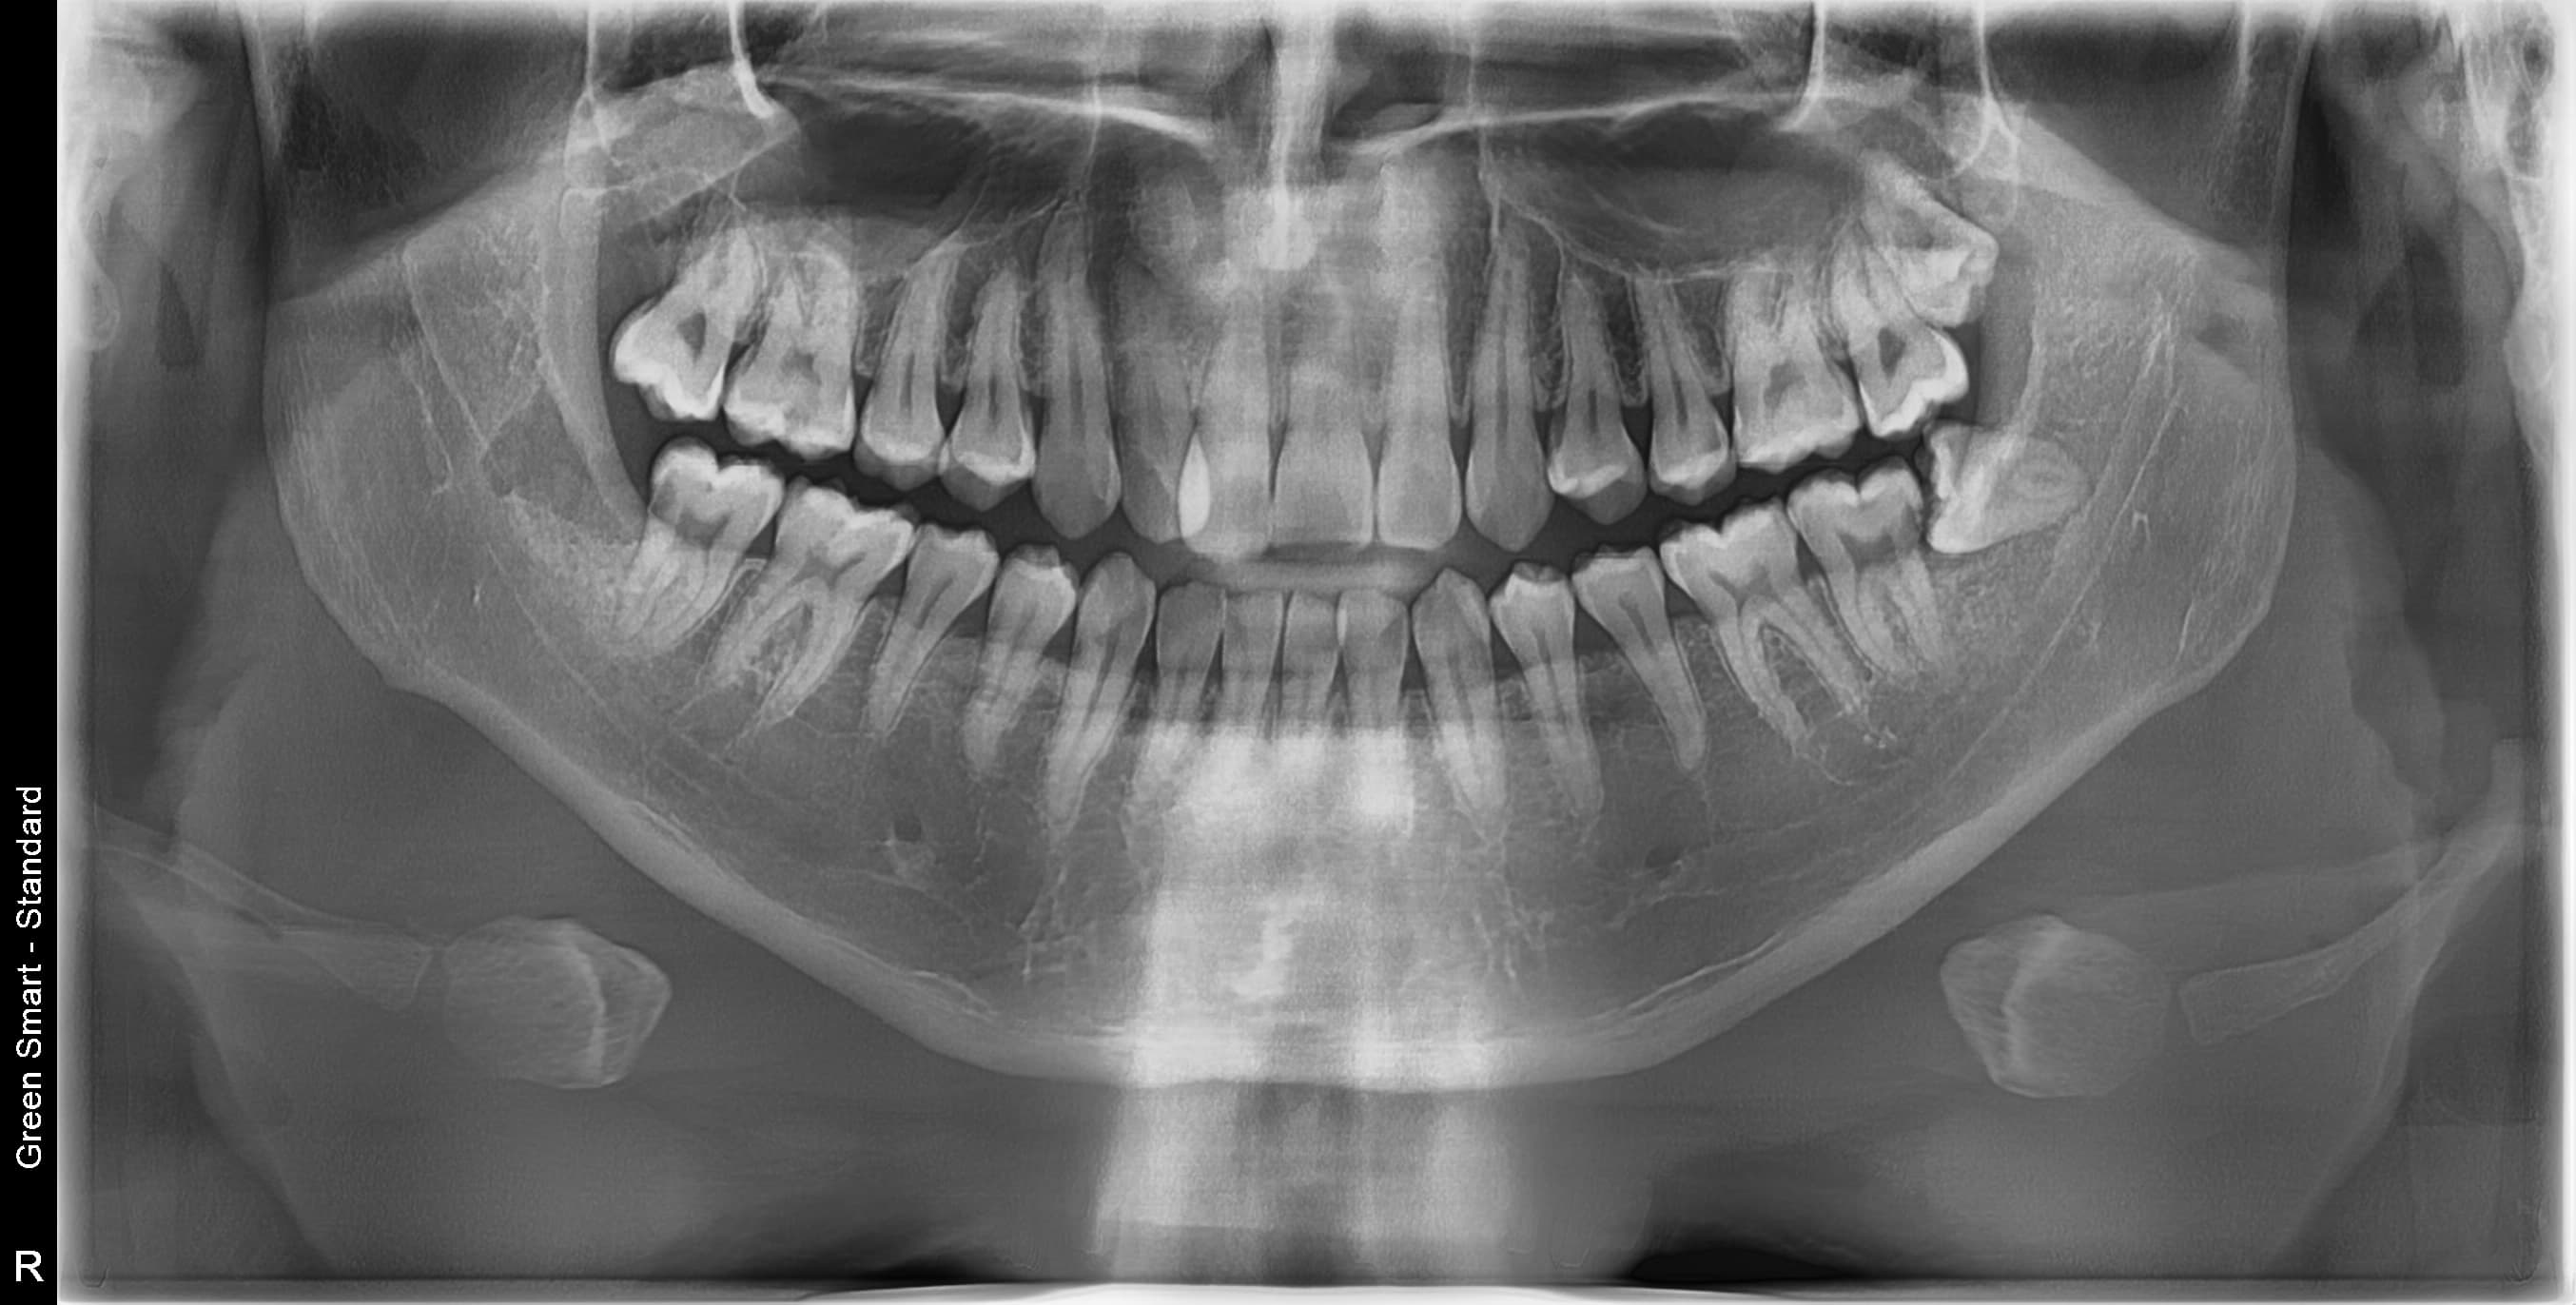

누운 사랑니

옆으로 누워 자라며 옆 치아를 압박할 수 있습니다

부분매복 사랑니

음식물이 끼기 쉽고 염증이 자주 발생합니다

완전매복 사랑니

낭종 형성 가능성이 있어 조기 발치가 필요합니다

치근만곡 사랑니

뿌리가 구부러져 있어 발치 난이도가 높습니다

수평매복 사랑니

앞 치아를 밀어 치열 불균형과 충치를 유발합니다